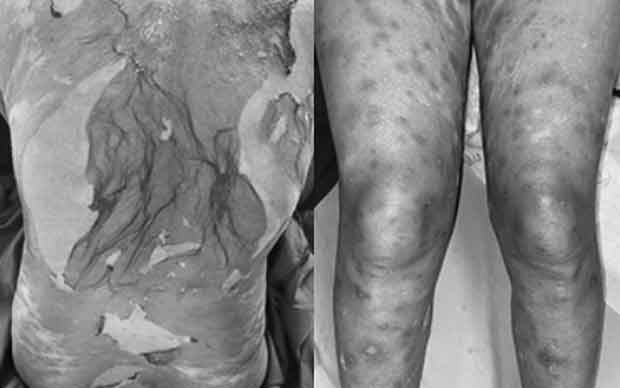

Theo thời gian, các thương tổn có tính chất tương tự xuất hiện thêm ở lòng bàn chân hai bên, thân mình, tay, chân, hoại tử da lan rộng. Các niêm mạc không có thương tổn. Bệnh nhân đau rát nhiều.

Bệnh nhân được chẩn đoán hoại tử thượng bì nhiễm độc (hội chứng Lyell) và điều trị tích cực tại khoa, dùng các thuốc đặc hiệu (cyclosporin A) kèm chăm sóc hỗ trợ. Sau 10 ngày điều trị, thương tổn da khô, bắt đầu tái tạo thượng bì, không có bọng nước mới.